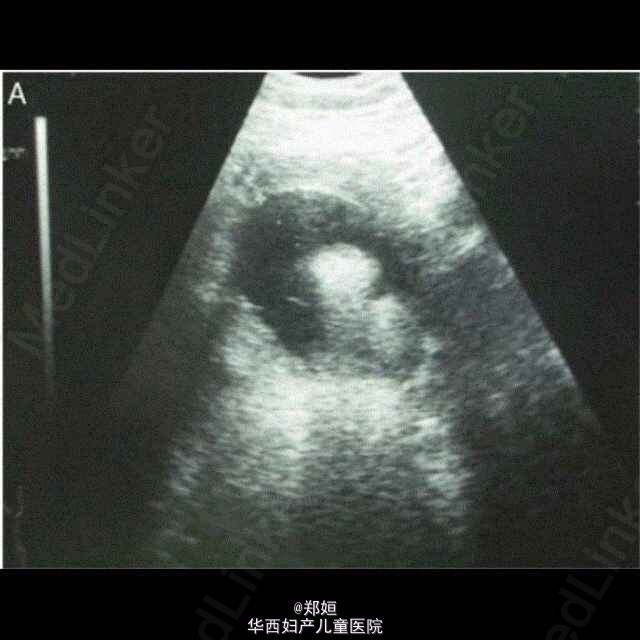

46岁女性,G2P2,腹部可触及包块。 通过超声可见2周内肿块直径从4.6cm长到了8.1cm。 CT示子宫体右侧有一肿瘤伴有脂肪组织。 初步诊断为畸胎瘤,行剖腹探查术。 术中可见肿瘤位于子宫底,完整未破裂,双侧卵巢肉眼观正常。